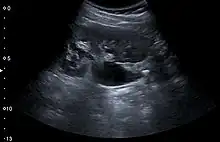

Figure 6. Complex cyst with thickened walls and membranes in the lower pole of an adult kidney. Measurements of kidney length and the complex cyst on the US image are illustrated by '+' and dashed lines.[1]

Complex cysts can have membranes dividing the fluid-filled center with internal echoes, calcifications or irregular thickened walls. The complex cyst can be further evaluated with Doppler US, and for Bosniak classification and follow-up of complex cysts, either contrast-enhanced ultrasound (CEUS) or contrast CT is used (Figure 6). The Bosniak classification is divided into four groups going from I, corresponding to a simple cyst, to IV, corresponding to a cyst with solid parts and an 85–100% risk of malignancy.[1] In polycystic kidney disease, multiple cysts of varying size in close contact with each other are seen filling virtually the entire renal region. In advanced stages of this disease, the kidneys are enlarged with a lack of corticomedullary differentiation (Figure 7).[1]